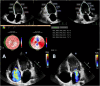

Case summary: We present the case of a 41-year-old female who was hospitalized for decompensated HF. Echocardiography revealed severe systolic dysfunction with a phenotype of dilated cardiomyopathy, accompanied by secondary moderate mitral regurgitation and severe tricuspid regurgitation (TR). To differentiate potential causes of HF, coronary angiography, cardiac magnetic resonance imaging (MRI), and endomyocardial biopsy were performed. Based on clinical findings, laboratory results, cardiac MRI, and endomyocardial biopsy data, a diagnosis of haemochromatosis was confirmed, and mutations in the TFR2 gene, responsible for haemochromatosis Type 3, were identified. The patient was treated in accordance with the latest European Society of Cardiology HF guidelines, and specific treatment for haemochromatosis, including therapeutic phlebotomy and iron chelation therapy, was initiated, resulting in a significant positive outcome.